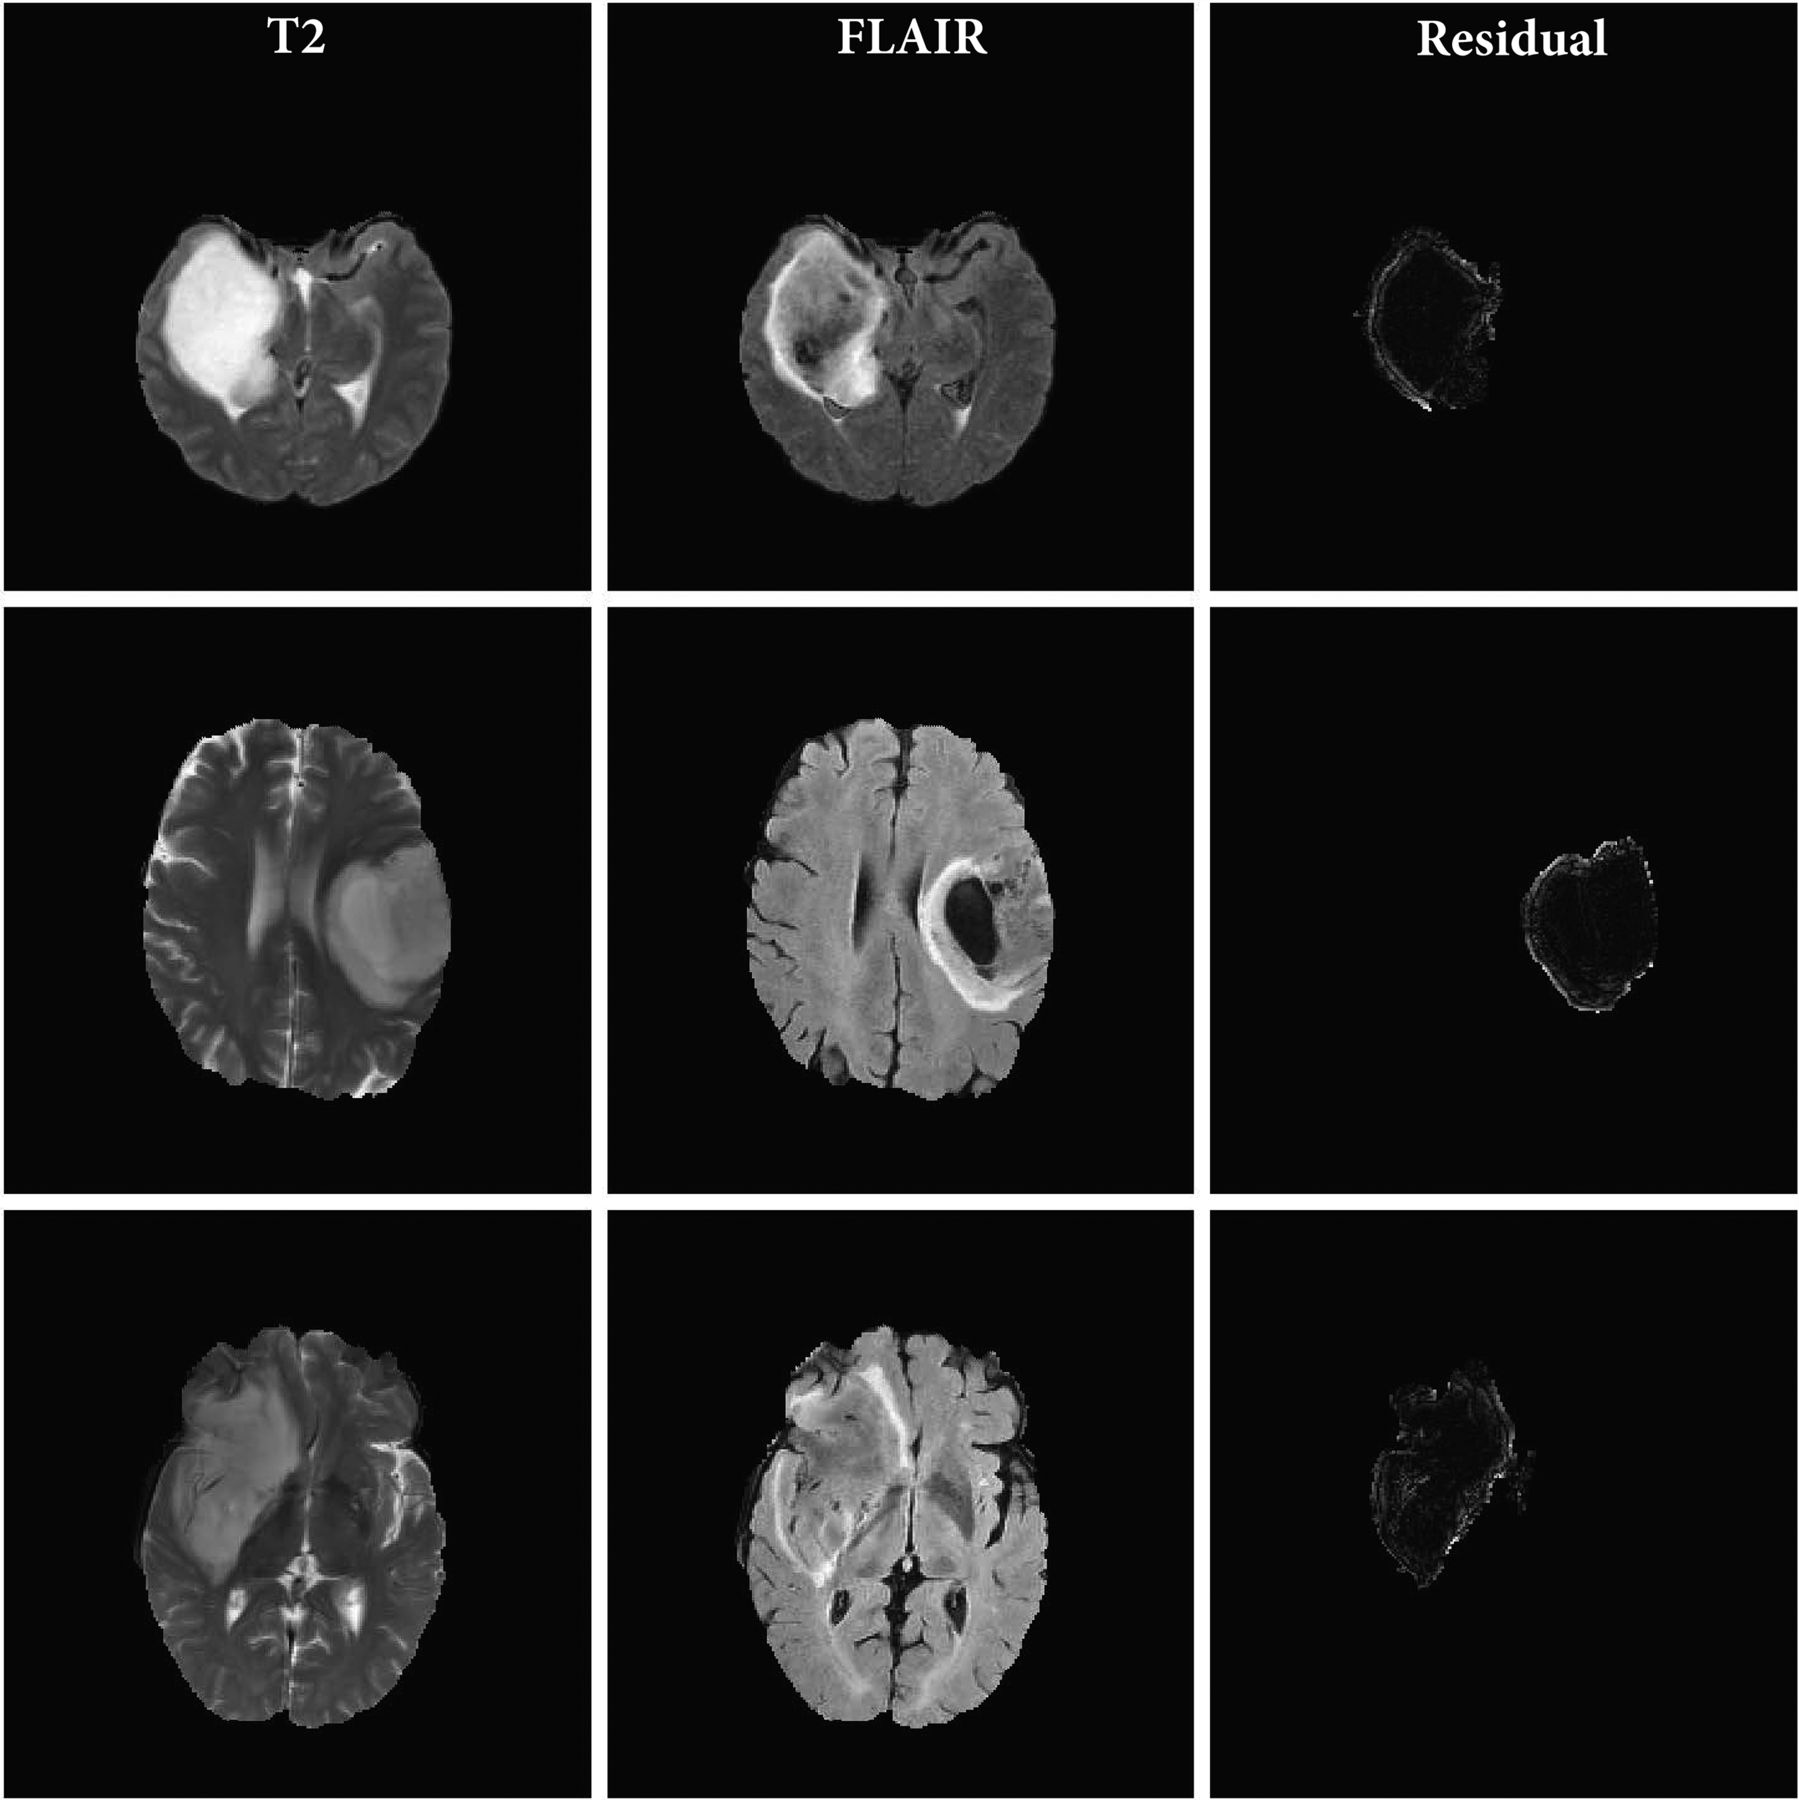

Figures 2 and 3 show the T2 TSE and FLAIR images and the pixel-wise GWR residual magnitudes from the tumor region for 3 sample cases with and without mismatch, respectively. We can see that the GWR residuals in Fig 2 clearly capture the hyperintense rim structure that is characteristic of a mismatch, whereas in Fig 3, there is no specific pattern to the GWR residuals but rather just a noisy distribution of pixel values over the tumor area. These images indicate that in cases with the mismatch, there is a clear difference in the axial rim along the boundary of the tumor between the T2 and FLAIR sequences.

T2 TSE and FLAIR MR images and the magnitude of the residual signatures corresponding to T2-FLAIR mismatch LGGs. Each row corresponds to an axial section from a patient tumor. The 3 columns represent the T2, FLAIR, and magnitude of the GWR residual for each tumor pixel, respectively.

Figures 2 and 3 capture the hyperintense rim structure that is characteristic of the T2-FLAIR mismatch signature. The visually observed differences in rim intensity are summarized in a figure in the Online Supplemental Data; cases having the T2-FLAIR mismatch have wider tails in their average PDFs than those without. This could be indicative of the high magnitude of residuals coming from the tumor rim. Given the high specificity of the mismatch signature to the IDH-mutant 1p/19q noncodeleted class of gliomas, we compared the residual signature of these cases with other classes. Most interesting, we observed significant differences in the average profile of this class of gliomas compared with other subtypes, regardless of their mismatch labels. Results from the permutation-based hypothesis test agree with visual differences in mean signatures. Specifically, comparisons (B) and (C) indicate significant differences in mean residual profiles of the IDH-mutated 1p/19q noncodeleted class of tumors. This result combined with the comparison (F) about differences within this subclass with and without mismatch indicate the utility of our approach. Our GWR-based approach is able to learn subtle features from the images that are difficult to discern visually. These features could potentially serve as sensitive markers for the IDH-mutant noncodeleted subtype of gliomas. To validate this hypothesis, we devised a classification algorithm using Euclidean representations (ie, principal component scores) of the T2-FLAIR GWR residual signatures.